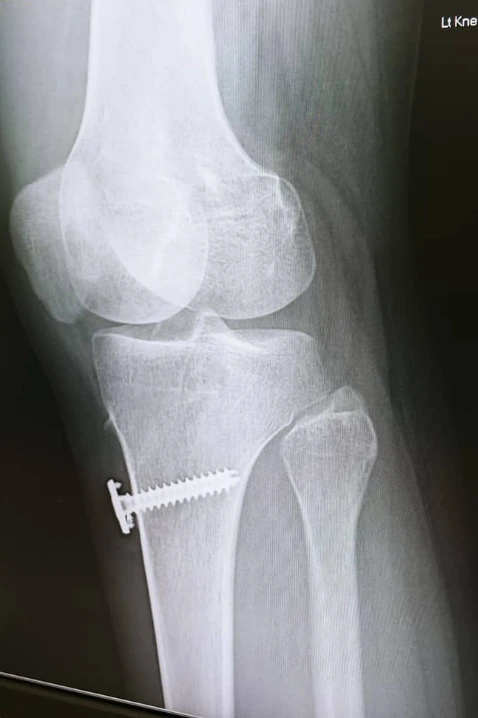

나의 다리 수술 때 박힌 나사 사진

사실 나는 몇 년 전 무릎 수술을 했다. 무릎 전방 십자 인대가 두 개다 완파되면서 두 달 가까이 병원에 누워있었고 몇 개월을 재활했지만, 다친 다리는 완전히 굽혀지지 않아 쪼그려 앉기가 되지 않았다.